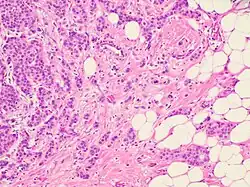

In the case of collective migration, cancer cells, being a part of the tumor mass or detaching from it in the form of multicellular groups, penetrate into the surrounding tissues and form thin, short chords, clusters, stripes and wide fields, as well as structures with lumen, that indicate a wide variety of structural elements involved in tumor invasion.[2]

Collective migration is characterized by the migration of whole cell groups interconnected by cadherins and intercellular gap junctions. A moving cell group has a “leading edge” or “leading front” that uses integrins and proteases. Observable differences exist in the expression of the genes and morphology between the “leader” cells forming the leading edge and the “follower” cells that are located behind them, at the “trailing edge”.[2] The cell shape of the “leaders” often resembles mesenchymal cells and is characterized by a less pronounced ordering and structural organization, while the “followers” tend to form more tightly packed, rosette-like tubular structures with tight intercellular contacts.[2]

Despite the structural diversity of the primary breast tumor, five main types of morphological structures can be distinguished: alveolar, trabecular, tubular and solid structures, and discrete groups of tumor cells. The alveolar structures are tumor cell clusters of round or slightly irregular shape. The morphology of the cells that form this type of structures varies from small cells with moderate cytoplasm and round nuclei to large cells with hyperchromatic nuclei of irregular shape and moderate cytoplasm. The trabecular structures are either short, linear associations formed by a single row of small, rather monomorphic cells or wide cell clusters consisting of two rows of medium-sized cells with moderate cytoplasm and round normochromic or hyperchromatic nuclei. The tubular structures are formed by a single or two rows of rather monomorphic cells with round normochromic nuclei. The solid structures are fields of various sizes and shapes, consisting of either small cells with moderate cytoplasm and monomorphic nuclei or large cells with abundant cytoplasm and polymorphic nuclei. Discrete groups of cells occur in the form of clusters of one to four cells with variable morphologies.[2]

The different morphological structures of breast tumors correspond to certain types of invasion. Therefore, alveolar, trabecular, and solid structures that are characterized by the presence of cell-cell contacts may be referred to morphological manifestations of collective migration, while discrete groups of tumor cells may be referred to manifestations of individual migration. The first batch of data obtained in a study of the expression of cell adhesion genes confirms this hypothesis. For example, there was a decrease in the activity of the genes of cadherins, which are responsible for cell-cell contacts, in the order: solid – alveolar and trabecular structures – discrete groups of tumor cells. In this case, the number of expressed genes of integrins involved in the adhesion of tumor cells to the extracellular matrix was reduced in the order: solid and alveolar – trabecular structures – discrete groups of tumor cells.[2]